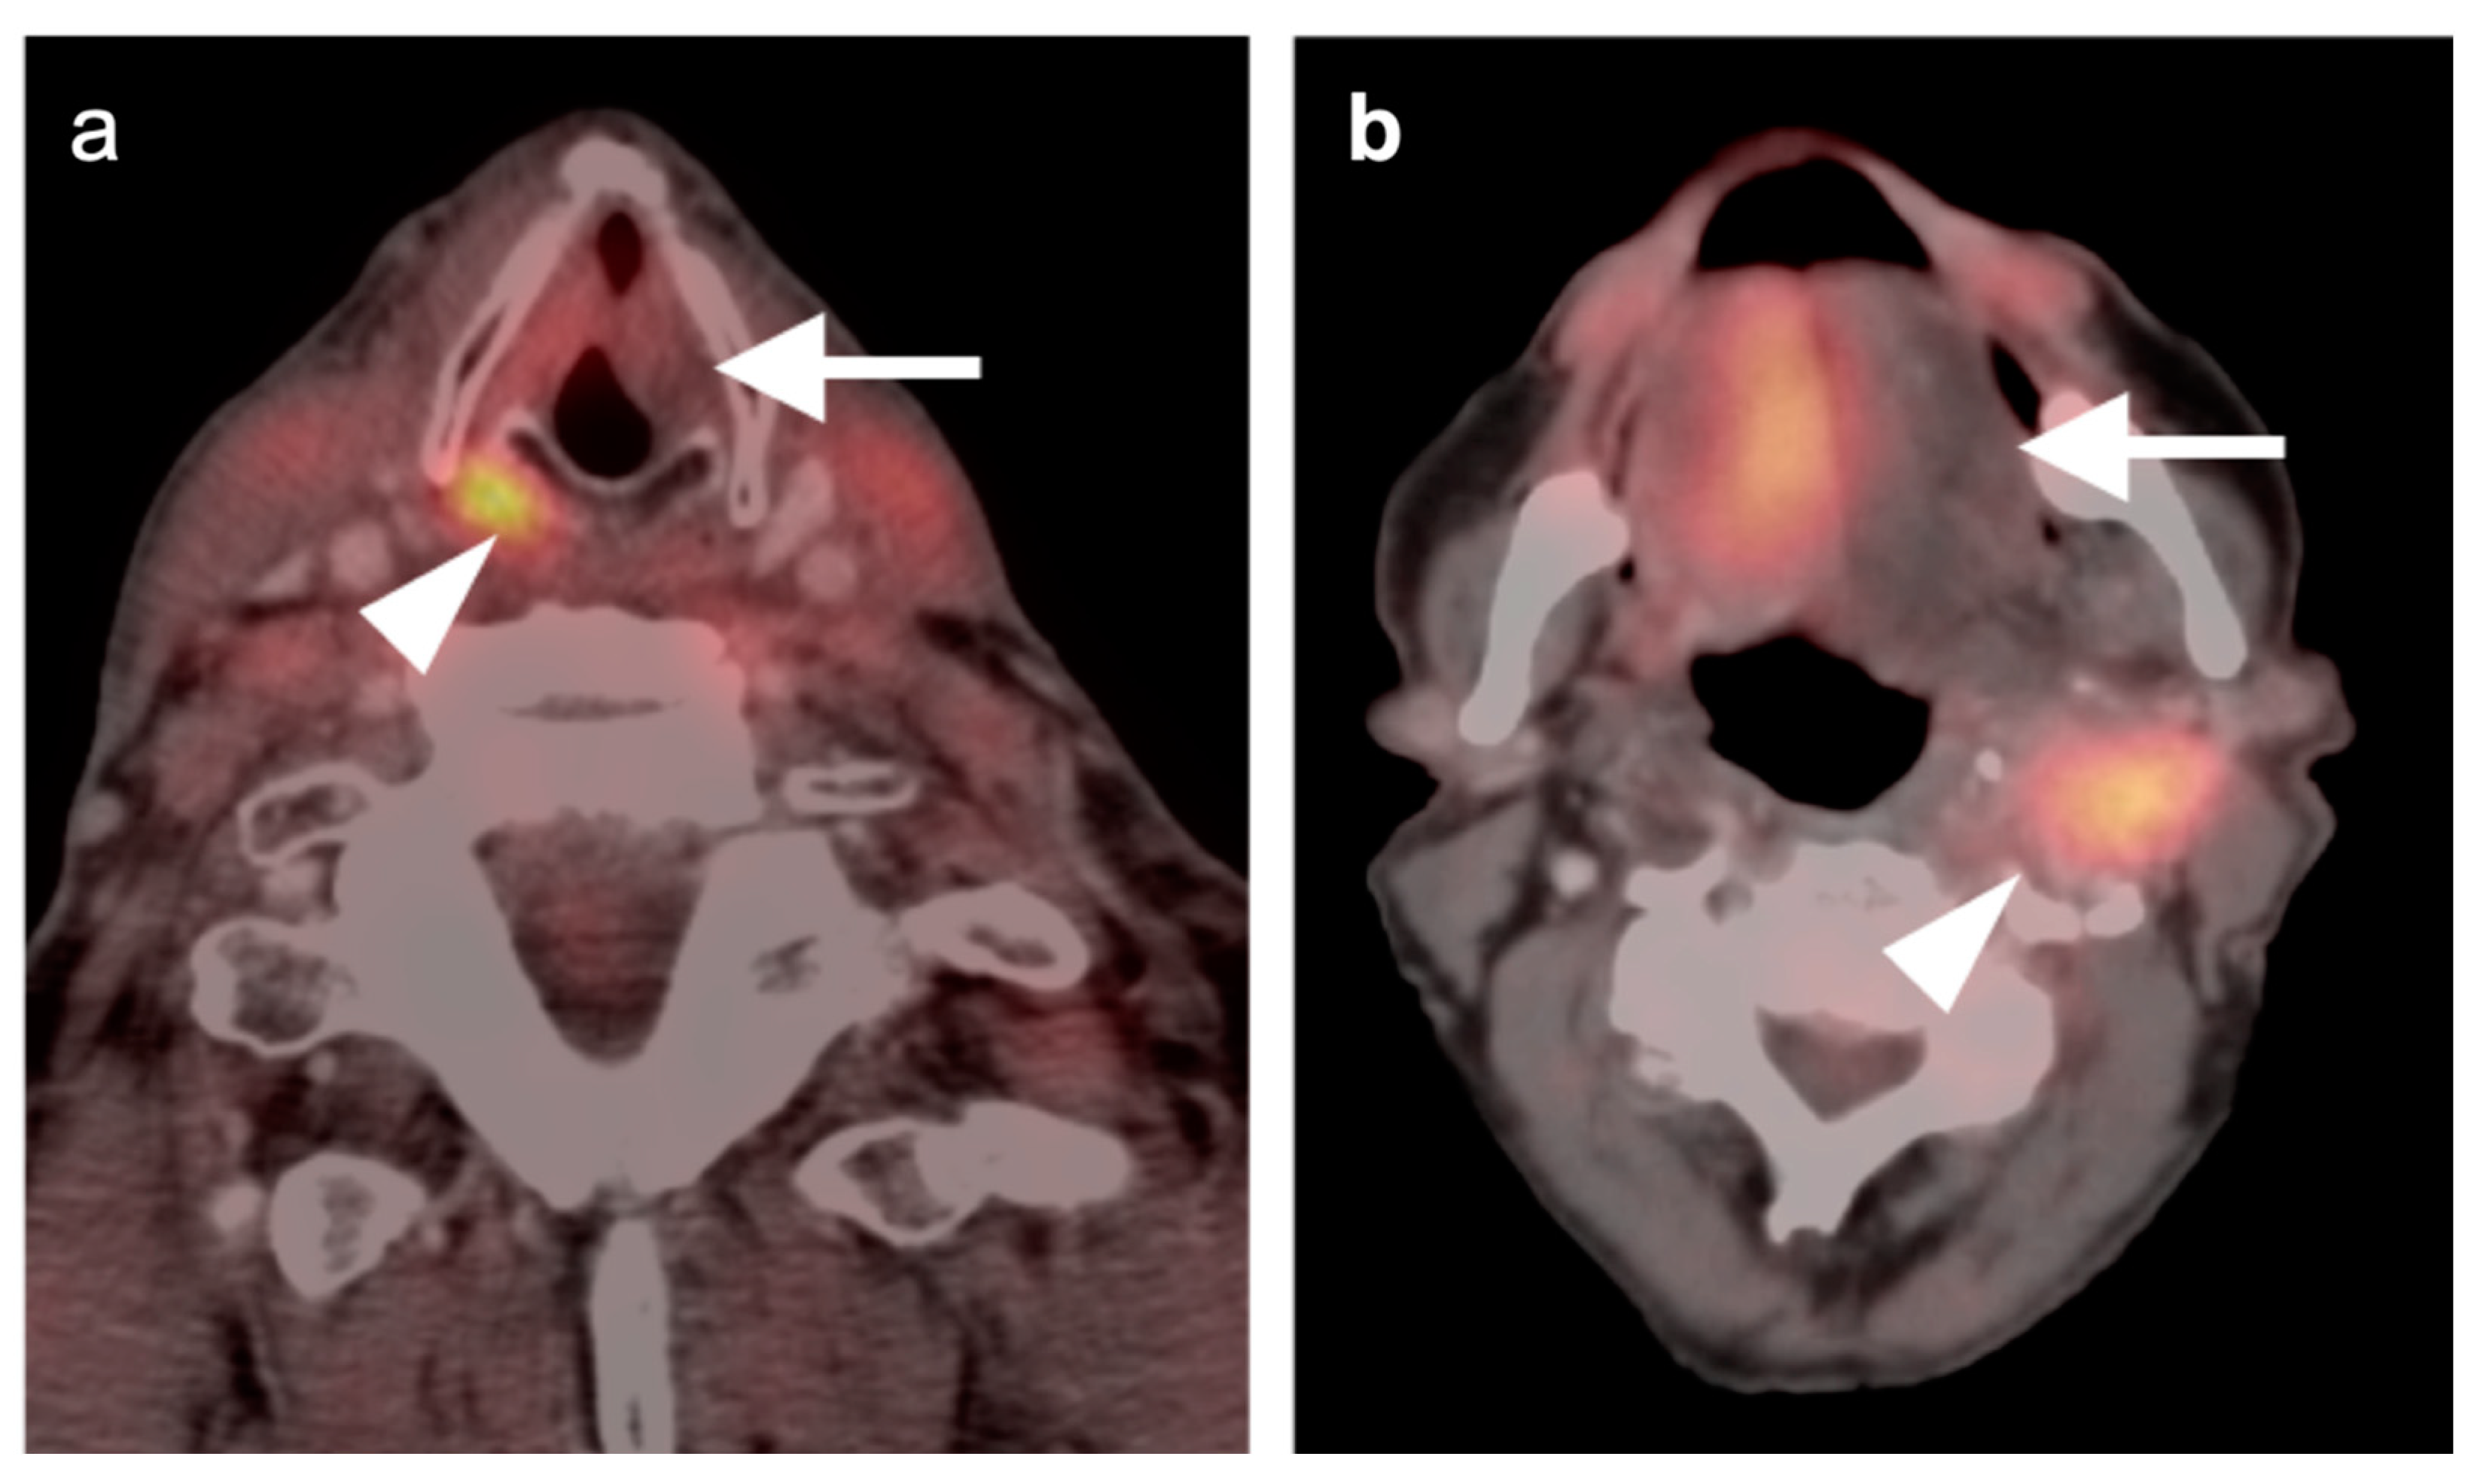

2.3. Nasopharyngeal Carcinoma

- Mohandas, A.; Marcus, C.; Kang, H.; Truong, M.-T.; Subramaniam, R.M. FDG PET/CT in the management of nasopharyngeal carcinoma. AJR Am. J. Roentgenol. 2014, 203, W146–W157. [Google Scholar] [CrossRef]